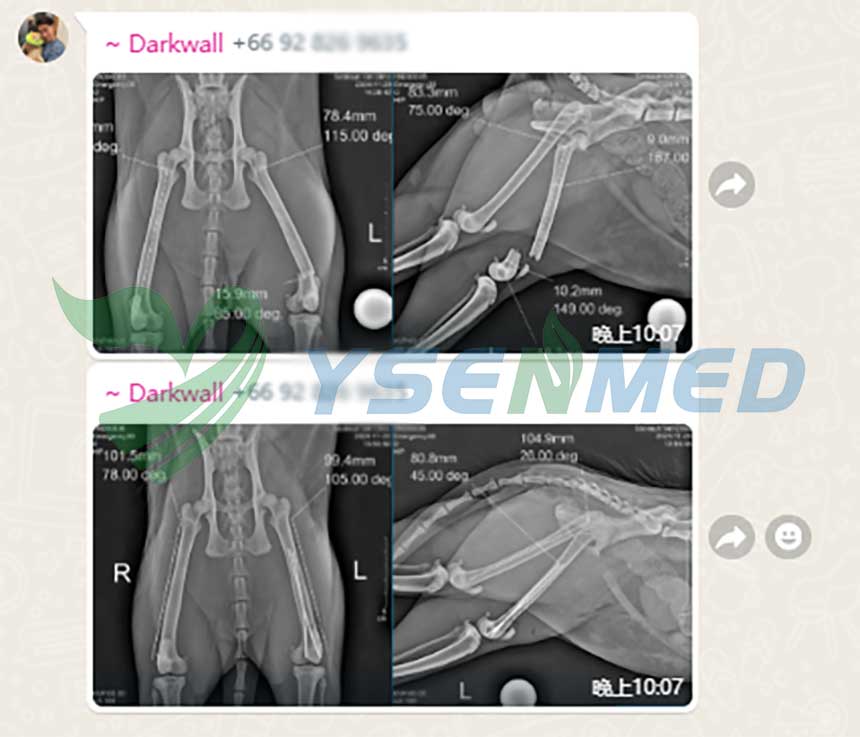

A Thai vet clinic digitizes its analog x-ray system with YSENMED YSFPD-M1717V VET flat panel detector, and the vet is very satisfied with the quality images and our after-sale service.